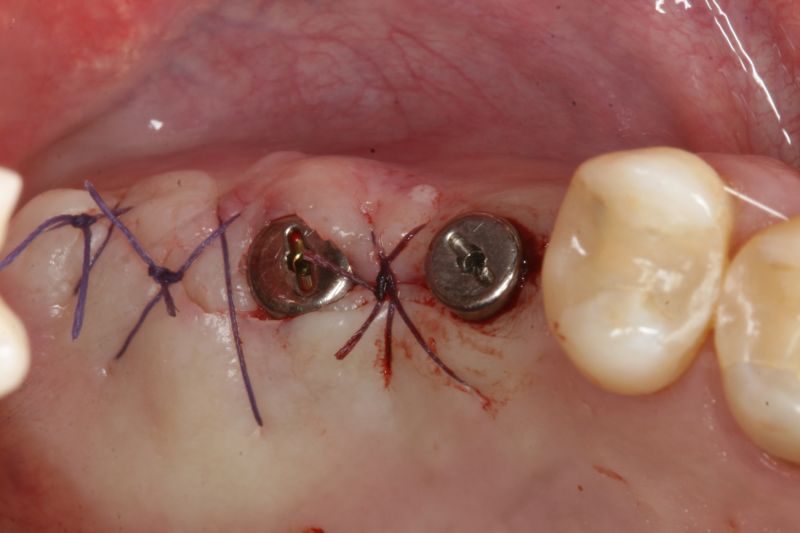

Immediate implant placement in the maxilla with contour GBR - Dr. K. Loukas

The patient presented with a terminal fracture of the crown tooth number 12